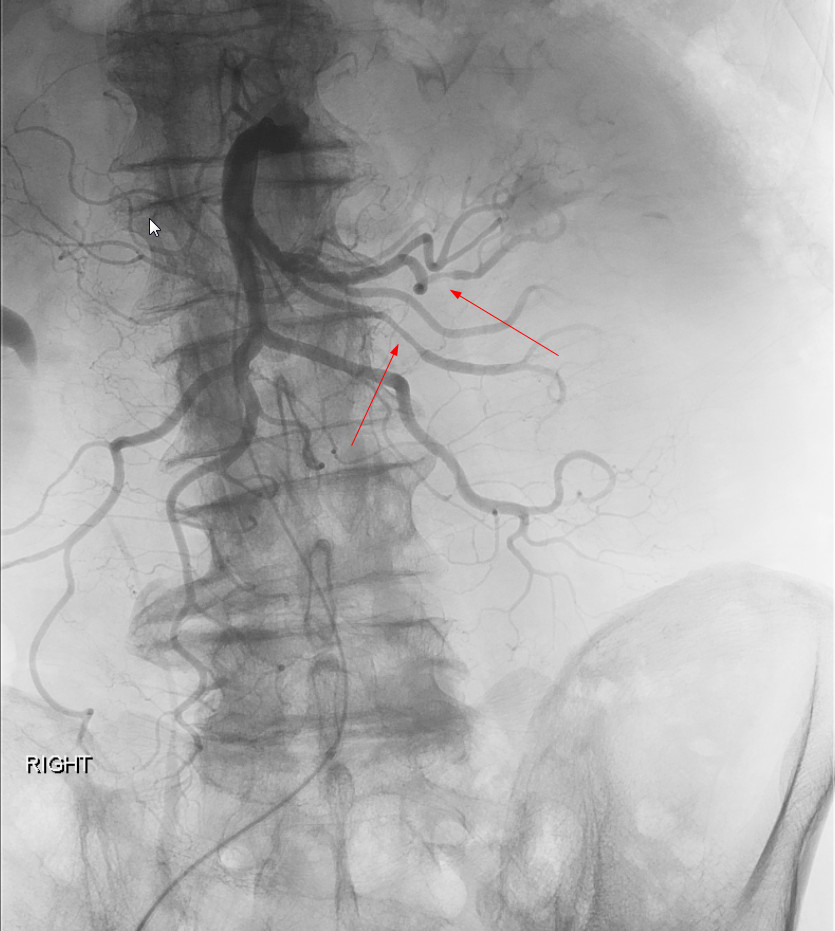

Case Presentation: 76-year-old male with a recent diagnosis of low-grade MDS presented to the hospital with complaints of severe fatigue, anorexia, abdominal pain and a 60 pound weight loss over six months. He also had a history of right foot drop 2 months prior with unclear etiology. He was subsequently hospitalized 1 month before presenting to our hospital with increasing abdominal pain, CT abdomen showed ileitis and mesenteric lymphadenopathy. He was treated with broad spectrum antibiotics with minimal improvement. Initial studies at our hospital showed pancytopenia with values near baseline, an elevated sedimentation rate of 82 mm/hr and C-reactive protein of 72.5. He had normal electrolytes, creatinine, copper, vitamin B 12 and vitamin-D levels. Urinalysis was within normal limits and serum protein electrophoresis did not show any monoclonal proteins. Complement and cryoglobulin levels were within normal limits. His serologies including ANA, ANCA, antiphospholipid antibody levels, hepatitis B and C were within normal limits. EMG of the lower extremities showed involvement of right distal sciatic nerve or both tibial and peroneal nerves. Colonoscopy revealed nonspecific inflammation of the colon. CT angiography revealed aortoiliac atherosclerosis but no evidence of vasculitis. Mesenteric angiogram was ordered due to high suspicion for vasculitis which revealed areas of narrowing along the superior & inferior mesenteric artery. This confirmed a diagnosis of polyarteritis nodosa (PAN). Following this the patient was given pulse dose steroids for 2 days followed by a slow taper. Further evaluation of MDS with T-cell receptor analysis was recommended.